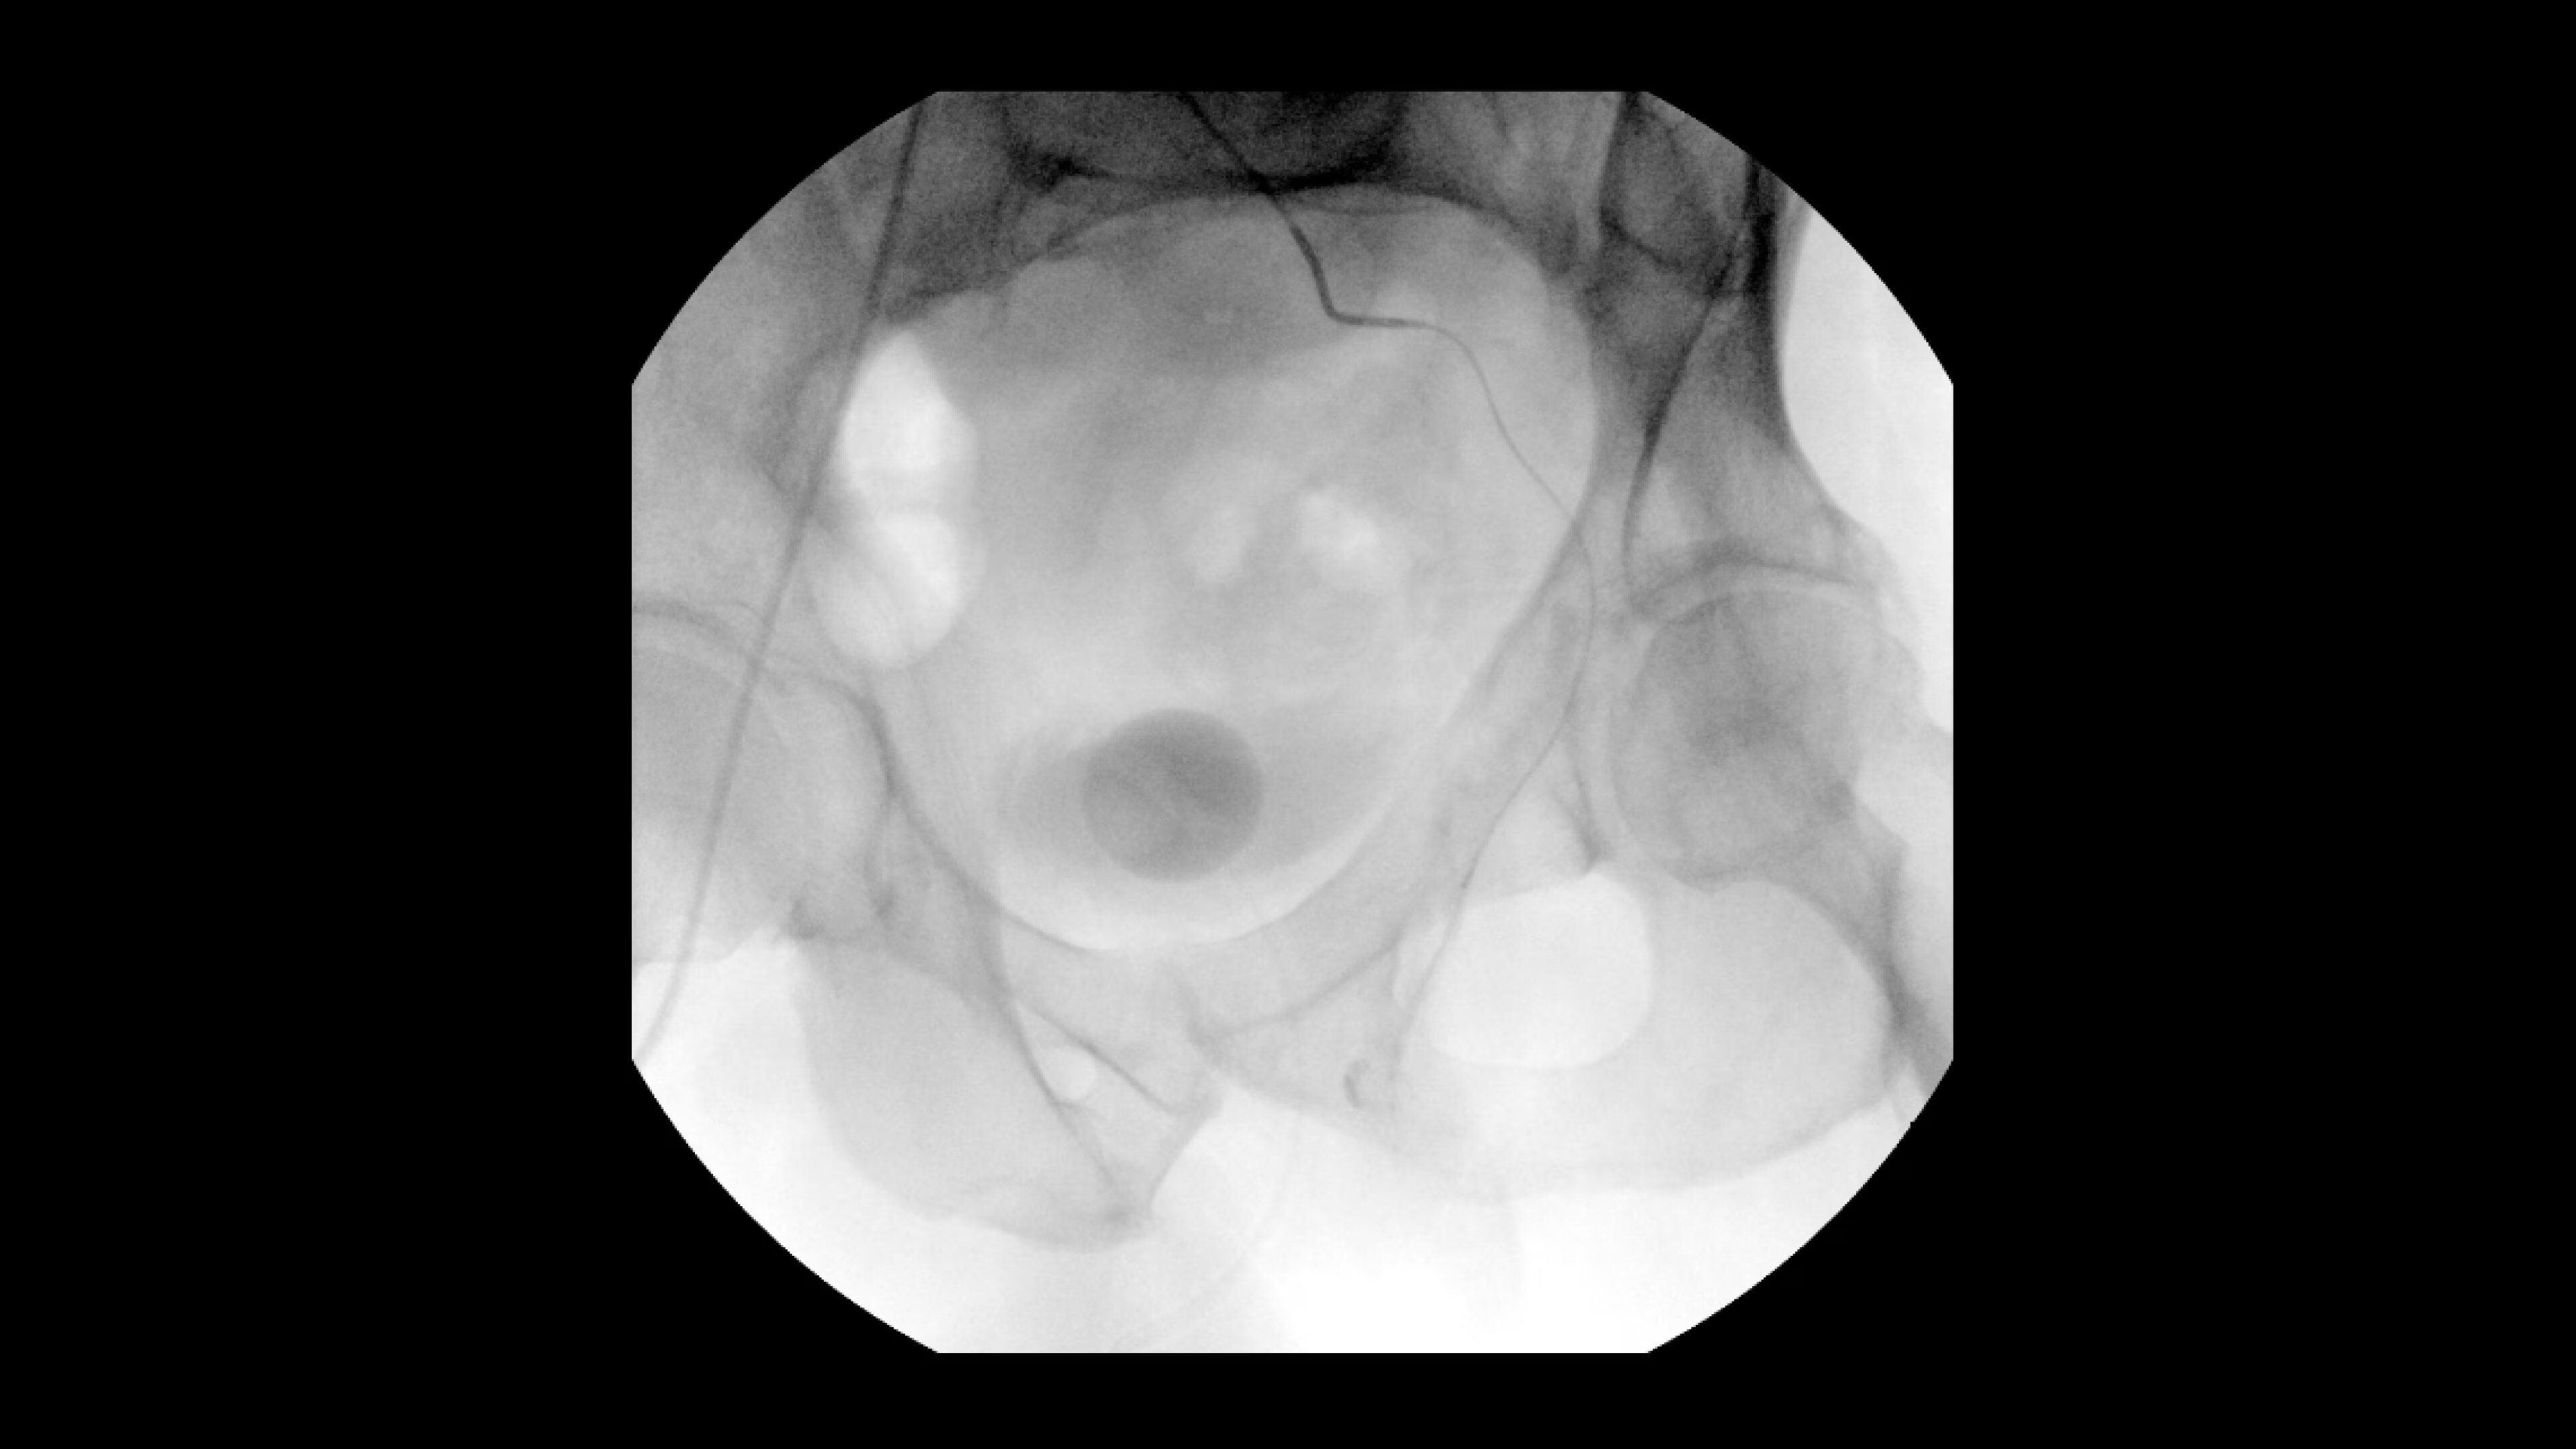

Interventional procedures require powerful imaging systems. OEC premium

C-arms perform in a variety of procedures such as:

• Prostatic Artery Embolization (PAE)

• Uterine artery embolization

• Pelvic congestion treatments

• Genicular artery embolization

• Venous leak embolization